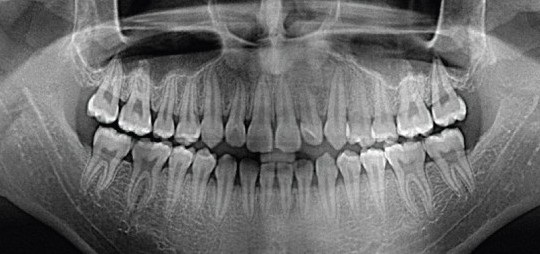

ОРТОПАНТОМОГРАФИЯ  В ЖЕЛЕЗНОДОРОЖНОМ

ОПТГ

Возможности ортопантомограмм (панорамных снимков)

Данные ортопантомограммы зубов позволяют оценить:

• Расположение зубов в челюстях и по отношению друг к другу, степень сформированности их корней;

• Положение, состояние и форму зубочелюстной кости;

• Структуру тканей, окружающих зубы;

• Стадию прорезывания зубов мудрости;

• Состояние и симметричность височно-нижнечелюстных суставов;

• Соотношение зубных рядов с нижнечелюстным нервом и гайморовыми пазухами;

• Состояние пломб, качество пломбировки каналов.

Выявить:

• Скрытые кариозные полости;

• Наличие дистопированных, ретенированных и сверхкомплектных зубов, адентию;

• Скрытые воспаления у верхушек корней зубов – гранулемы, кисты;

• Патологические изменения пародонта.

Проконтролировать:

• Процесс лечения кривых зубов, точность и эффективность;

• Процесс прорезывания зубов, развития зубных пластинок у детей с временным прикусом.

В МЦ "ГЕРАТ" Панорамный снимок челюсти выполняется на специальном цифровом рентгеновском аппарате Veraviewepocs 3D созданным компанией J. Morita .  Панорамный снимок зубов делается в цифровом виде, снимок заносится в компьютерную карту пациента и любой специалист клиники может быстро просмотреть его для уточнения диагноза и планирования лечения. При необходимости консультации с врачами в других клиниках производится печать панорамного снимка зубов на бумаге или запись результатов на электронный носитель. Наличие компьютерного томографа в МЦ "ГЕРАТ" дает возможность получить панорамный снимок более высокой точности.